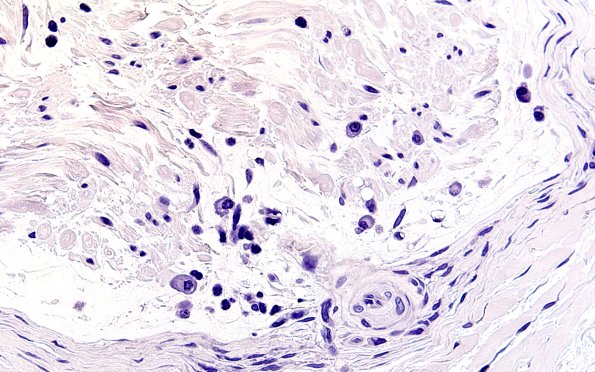

Washington University Experience | PERIPHERAL NEUROPATHY | 12 ANTI-MAG NEUROPATHY | 1B4 Anti-MAG Neuropathy (Case 1) Neg Control 60X 1

There are numerous plasma cells within the endoneurium. Do they correlate with the extent of myelinopathy by directly contributing to the intra-axonal titers of anti-MAG antibody? (negative immunostain)